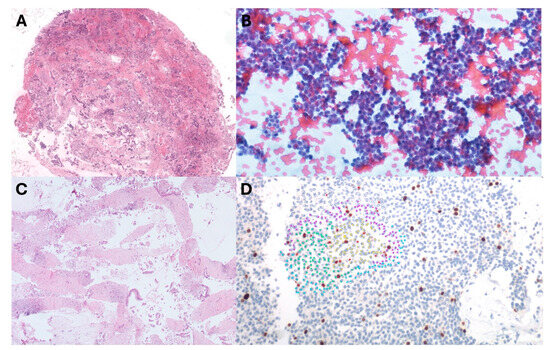

3.4. Diagnostic Accuracy

3.8. Feasibility of Ki-67 in Pan-NETs